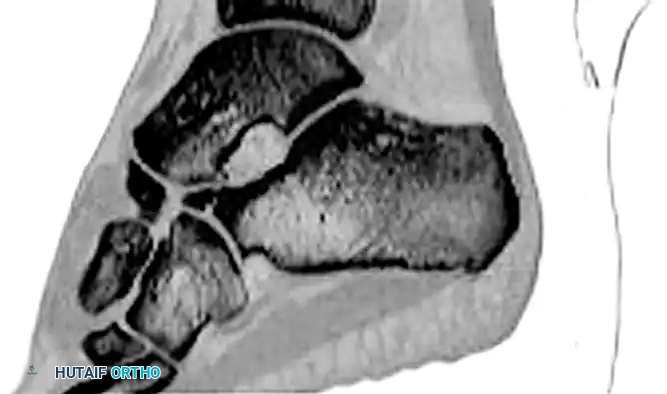

Cross-Sectional Intraosseous Vascular Mapping

The intraosseous distribution of these vessels is complex. The following series of diagrams illustrates the sagittal and coronal perfusion zones of the talus, highlighting the critical watershed areas within the talar body.

Image

VASCULAR ANATOMY OF THE TALUS

The vascular anatomy of the talus has been extensively studied and mapped, most notably by Mulfinger and Trueta. The three major arteries of the leg—the anterior tibial, posterior tibial, and peroneal arteries—contribute to a rich, extraosseous, anastomotic plexus that supplies blood to the head, neck, and body of the talus.

Clinical Pearl: The overall contribution of the blood supply to the talus is distributed as follows: posterior tibial artery (47.0%), anterior tibial artery (36.2%), and peroneal artery (16.9%). The anterior tibial artery is the primary supplier to the anteromedial quadrant, while the posterior tibial artery dominates the remaining three quadrants.